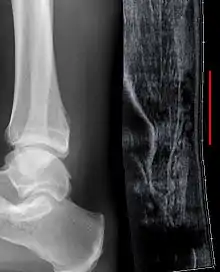

Sometimes an ultrasound scan may be required to clarify or confirm the diagnosis and is recommended over MRI.[11] MRI is generally not needed.[12]

Musculoskeletal ultrasonography can be used to determine the tendon thickness, character, and presence of a tear. It works by sending extremely high frequencies of sound through the body. Some of these sounds are reflected back off the spaces between interstitial fluid and soft tissue or bone. These reflected images can be analyzed and computed into an image. These images are captured in real time and can be very helpful in detecting movement of the tendon and visualising possible injuries or tears. This device makes it very easy to spot structural damages to soft tissues, and consistent method of detecting this type of injury. This imaging modality is inexpensive, involves no ionizing radiation and, in the hands of skilled ultrasonographers, may be very reliable.

Radiography can also be used to indirectly identify Achilles tears. Radiography uses X-rays to analyse the point of injury. This is not very effective at identifying injuries to soft tissue. X-rays are created when high energy electrons hit a metal source. X-ray images are acquired by utilising the different attenuation characteristics of dense (e.g. calcium in bone) and less dense (e.g. muscle) tissues when these rays pass through tissue and are captured on film. X-rays are generally exposed to optimise visualisation of dense objects such as bone while soft tissue remains relatively undifferentiated in the background. Radiography has little role in assessment of Achilles' tendon injury and is more useful for ruling out other injuries such as calcaneal fractures.[13]